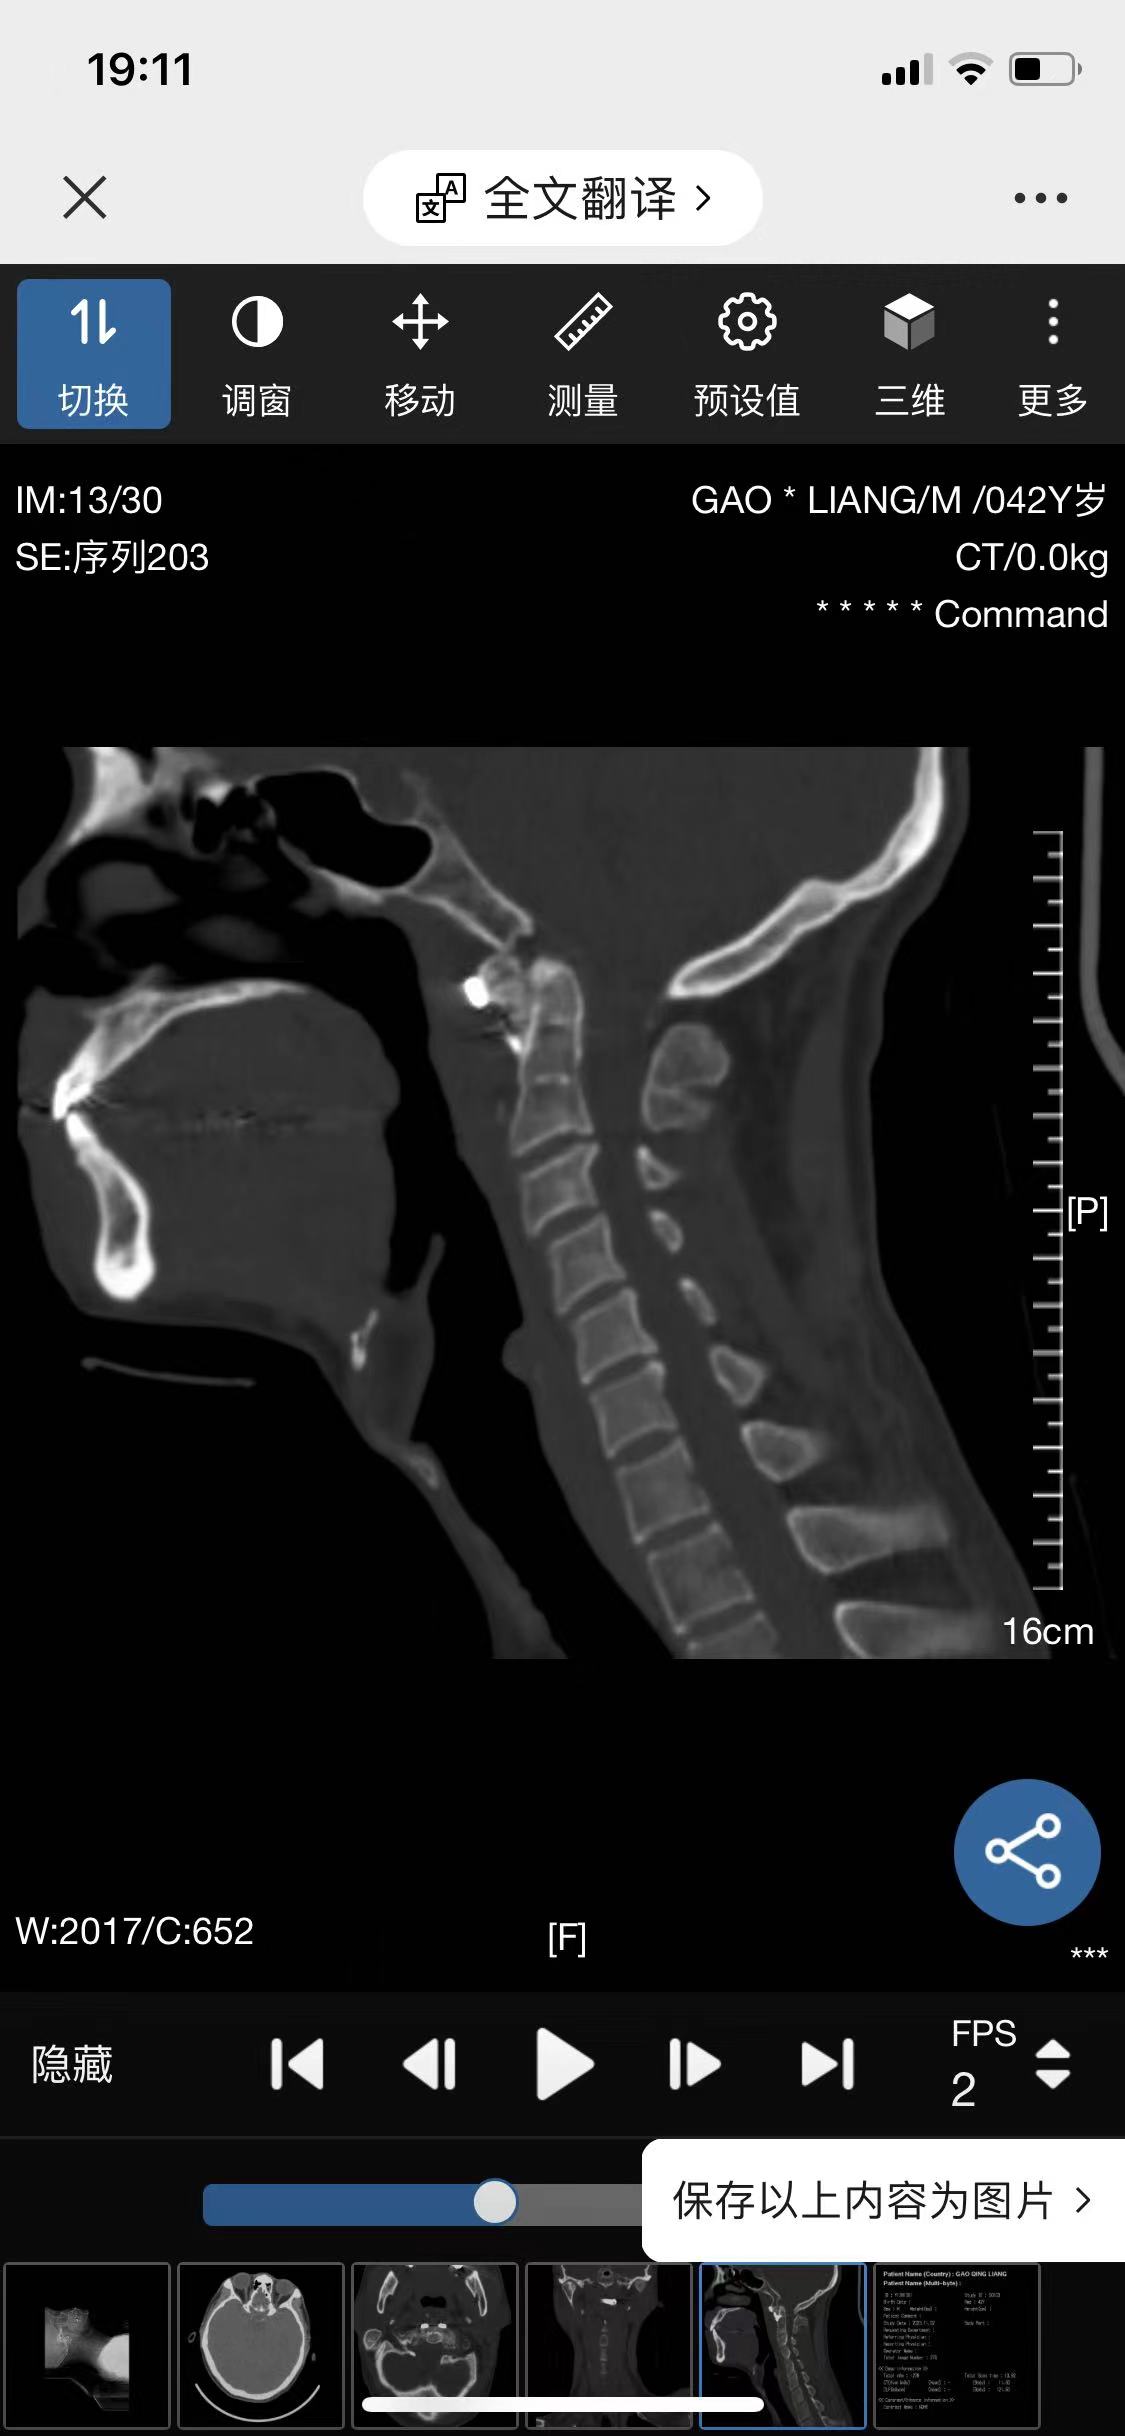

• 诊断:寰枢椎脱位

• 影像:

• 术后影像: